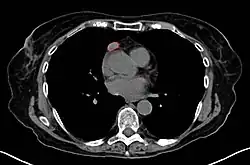

Ante la sospecha de un timoma, generalmente se realiza una TC para valorar el tamaño y extensión del tumor, a este se le puede tomar una muestra a través de una biopsia guiada por radiología. El realce vascular incrementado en la TC puede ser indicativo de malignidad, así como la presencia de derrame pleural.[1] La toma de biopsia esta asociada con un pequeño riesgo de neumomediastino o mediastinitis e incluso un riesgo aún menor de daño cardíaco o a los grandes vasos. Algunas veces el timoma puede tener metástasis en el abdomen.[6]